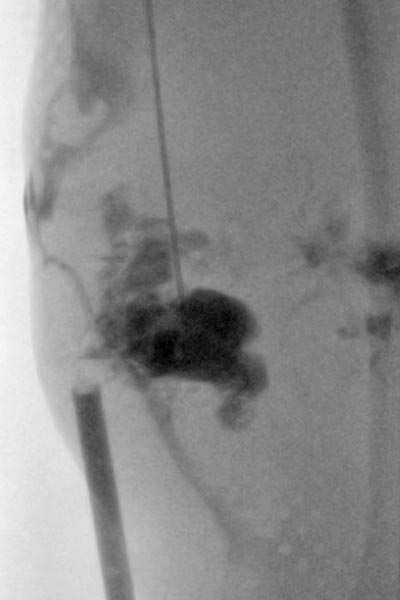

Es erfolgte wegen des deutlichen Progresses und den sich immer wieder entzündenden, schmerzhaften Anteilen eine Sklerosierungstherapie mit Doxycyclin (Konzentration 10 mg/ml) der zystischen Anteile. Das Durchleuchtungsbild zeigt die Punktion und Kontrastierung der Zysten vor Injektion des Sklerosierungsmittels.

Da das klinische Ergebnis noch nicht zufriedenstellend war, erfolgte eine erneute Sklerosierungsbehandlung (hier das zugehörige Durchleuchtungsbild nach Kontrastmittelinjektion in die Läsion). Eine notwendige Wiederholung war anhand der Größe der Läsion auch von vornherein zu erwarten. Diesmal gleichzeitig mit einer lokalen sonographisch gesteuerten Biopsieentnahme zur histopathologischen Subdifferenzierung der Slow-flow-Gefäßmalformation.